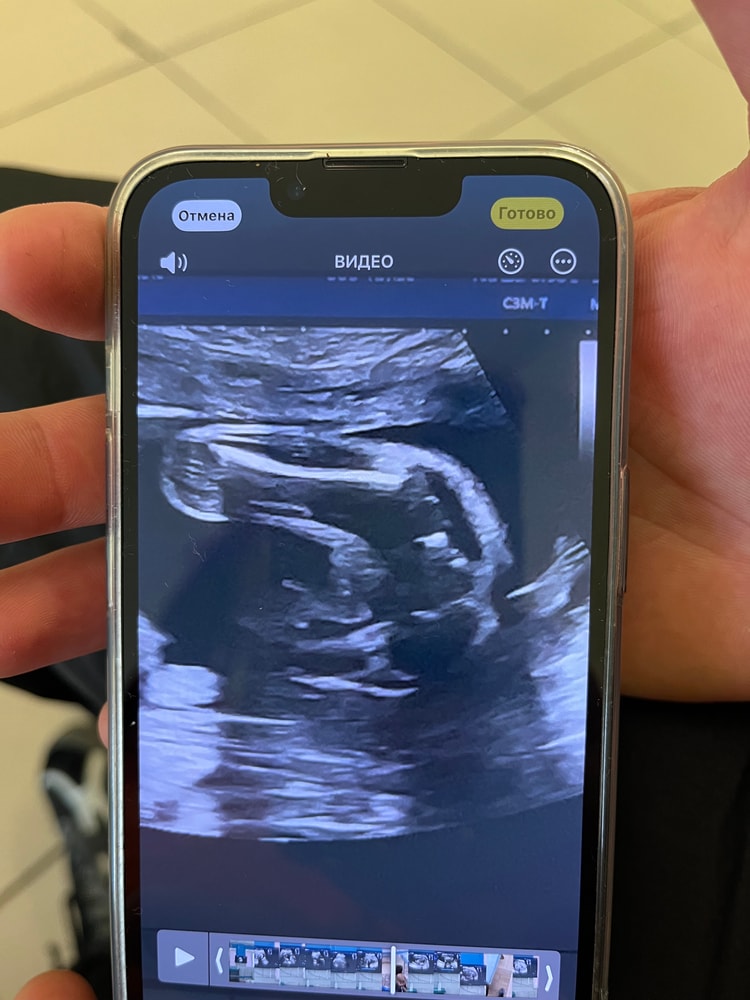

Кто видит мальчик или девочка?

Пол малышаДевочки, сходила на узи, посмотрели, сказали - мальчик. Но я пересматриваю и никакого мальчика не вижу. Типо яички так, а писюн где??? Может это я себя так уже накрутила, потому что девочку хотела, 2 мальчика уже есть. Но кто сможет мне сказать?

Я комменты не читала, по фото вижу мальчика, вид снизу. Это мошонка со стороны попы, а писюн как бы сверху, поэтому не виден так отчетливо. У меня девочка точно с такого же ракурса выглядела иначе, там прям видны половые губы. А тут яички

У вас не очень информативное изображение 🙁 подождите пару недель или сходите на другое узи

Я тоже вижу пирожок,с пацанами у них торчал писюн еще,сложно не заметить было

специально подчеркнула , где яички и где писюн. Мне кажется мальчик . Муж ваш доминантный походу.

На таком сроке вряд ли ошибка, но по фото мне тоже больше девочку напоминает.

Вот у меня на узи сын))у вас не могу понять,как-будто и да,а как-будто и нет,но больше склоняюсь,что вижу мужские половые органы